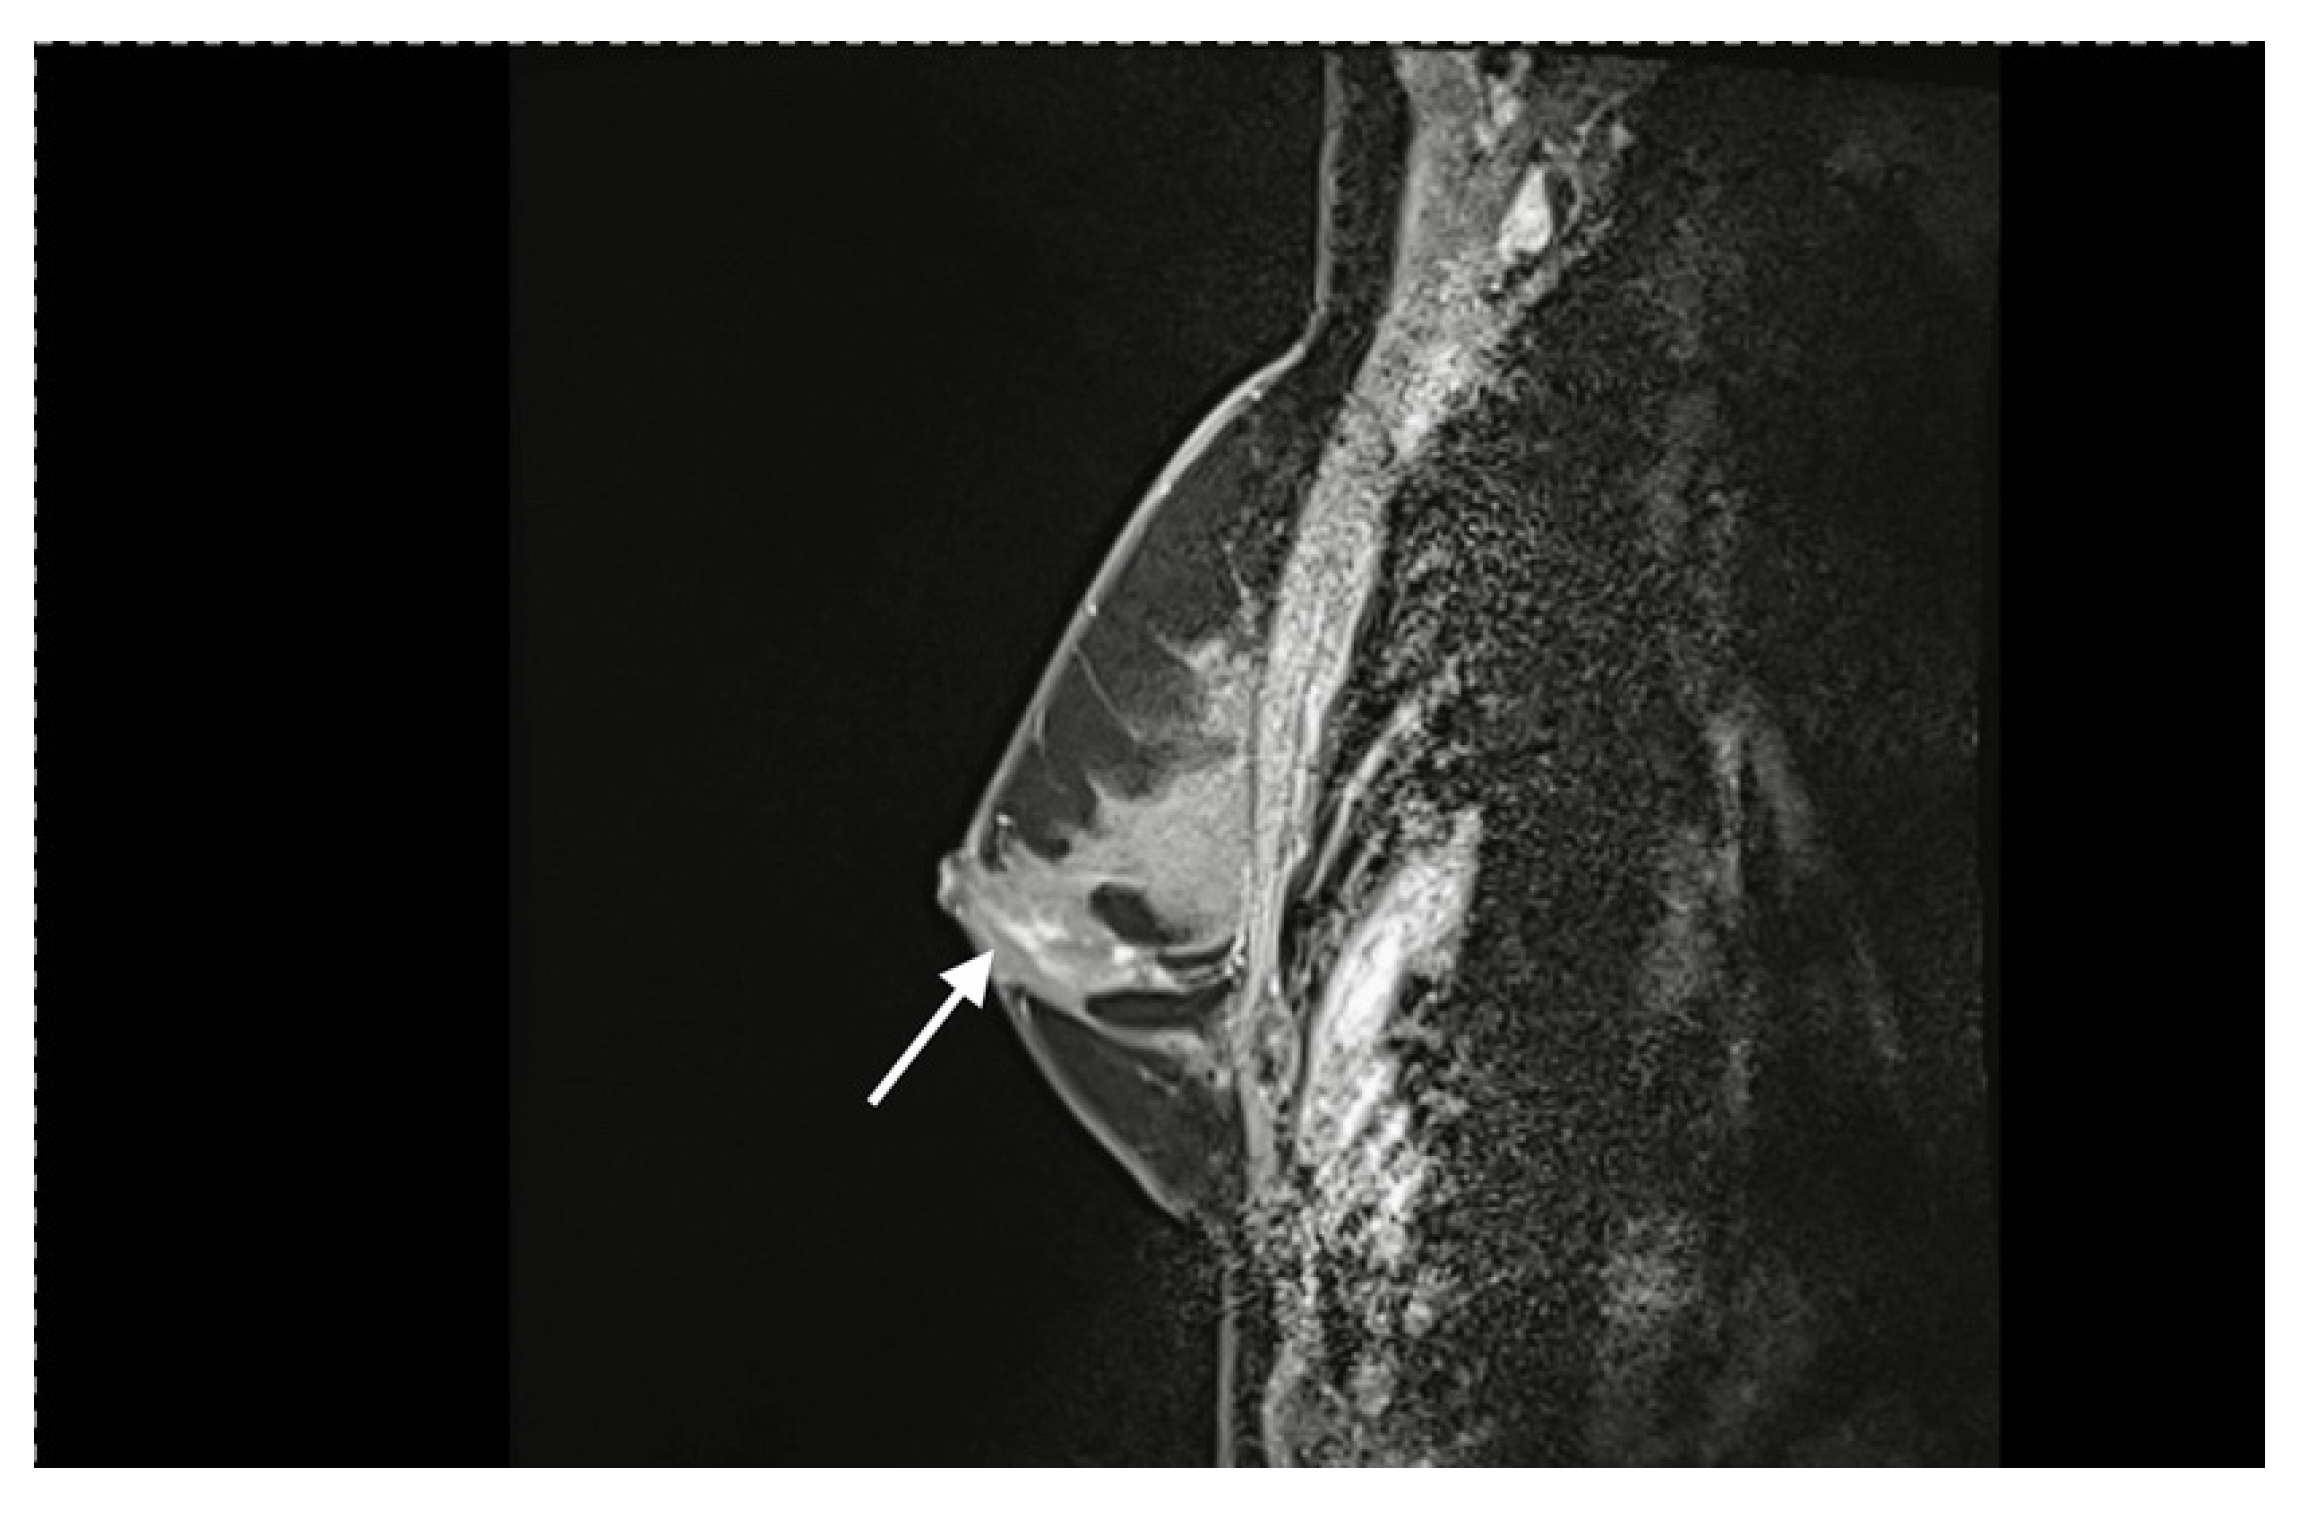

- Ptotic/Large breasts: In ptotic breasts (minimal to moderate ptosis) or large breasts, the reconstruction results in less volume. The breast is measured preoperatively in a standing position. The new NAC position is marked. The upper edge should not be higher than 6–8 cm from the upper breast border. The distance between the lower edge of the NAC and the IMF should be equal to the volume of the flap. For a smaller breast, about 6–7 cm—for a larger one, 7–8 cm.